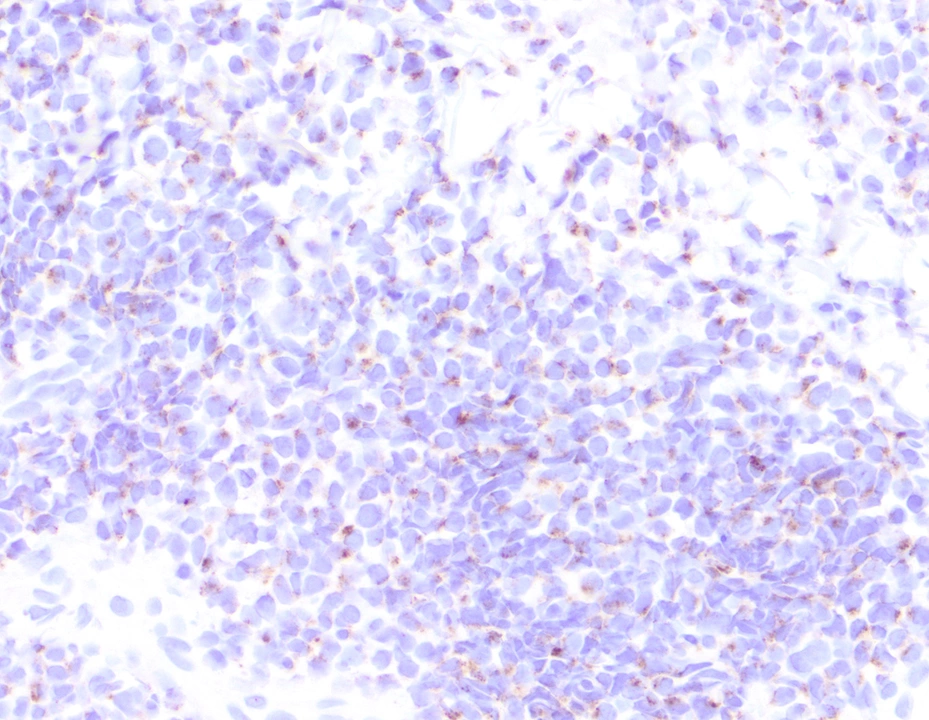

Микропрепараты: Лимфогранулематоз и Нодулярный Склероз

Раздел: Секреты мастерства